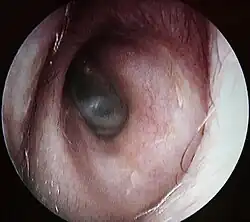

Bouchon de cérumen complet dans le conduit auditif